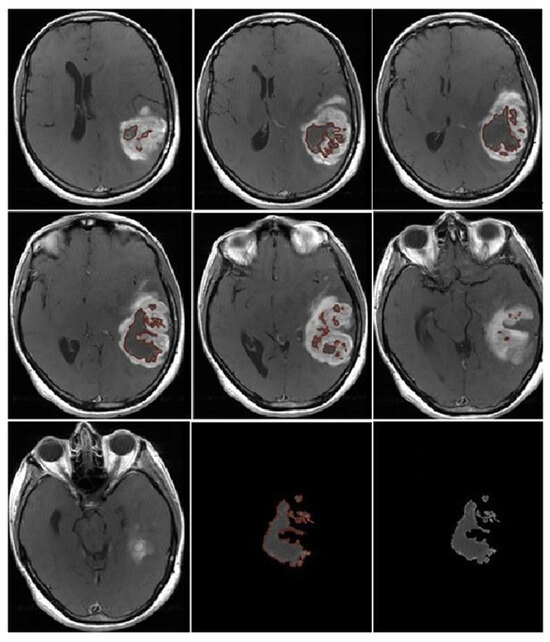

- Morphological appearance: We divided GB lesions into three categories based on the enhancing wall thickness: thin, <3 mm; thin-nodular, when the enhancing wall showed focal thickenings > 3 mm; and nodular, when solid appearance was predominant and intratumoral necrosis was absent or <1.5 cm3. A total of 11 (13%) masses showed a thin pattern, 51 (58%) showed a thin-nodular pattern, and 25 (29%) showed a nodular pattern.

- Multifocal disease: Multifocal disease was found in 20 (23.3%) patients (Table 1).